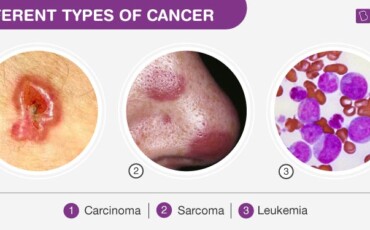

A group of diseases characterized by the uncontrolled growth of abnormal cells in the body. Cancer can affect various organs and systems, requiring tailored treatment approaches.